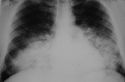

29 year old male with 1 month history of Progressively increasing dyspnoea, Cough with mucoid sputum

Working in a petrol pump, but no obvious exposure to dust, smoke, pets

Clinically stable :

ABCs normal, Vitals stable, AEBE, B/L Creps +

Bilateral symmetric alveolar opacities located centrally in mid and lower lung zones are typical, often in a "bat wing" distribution